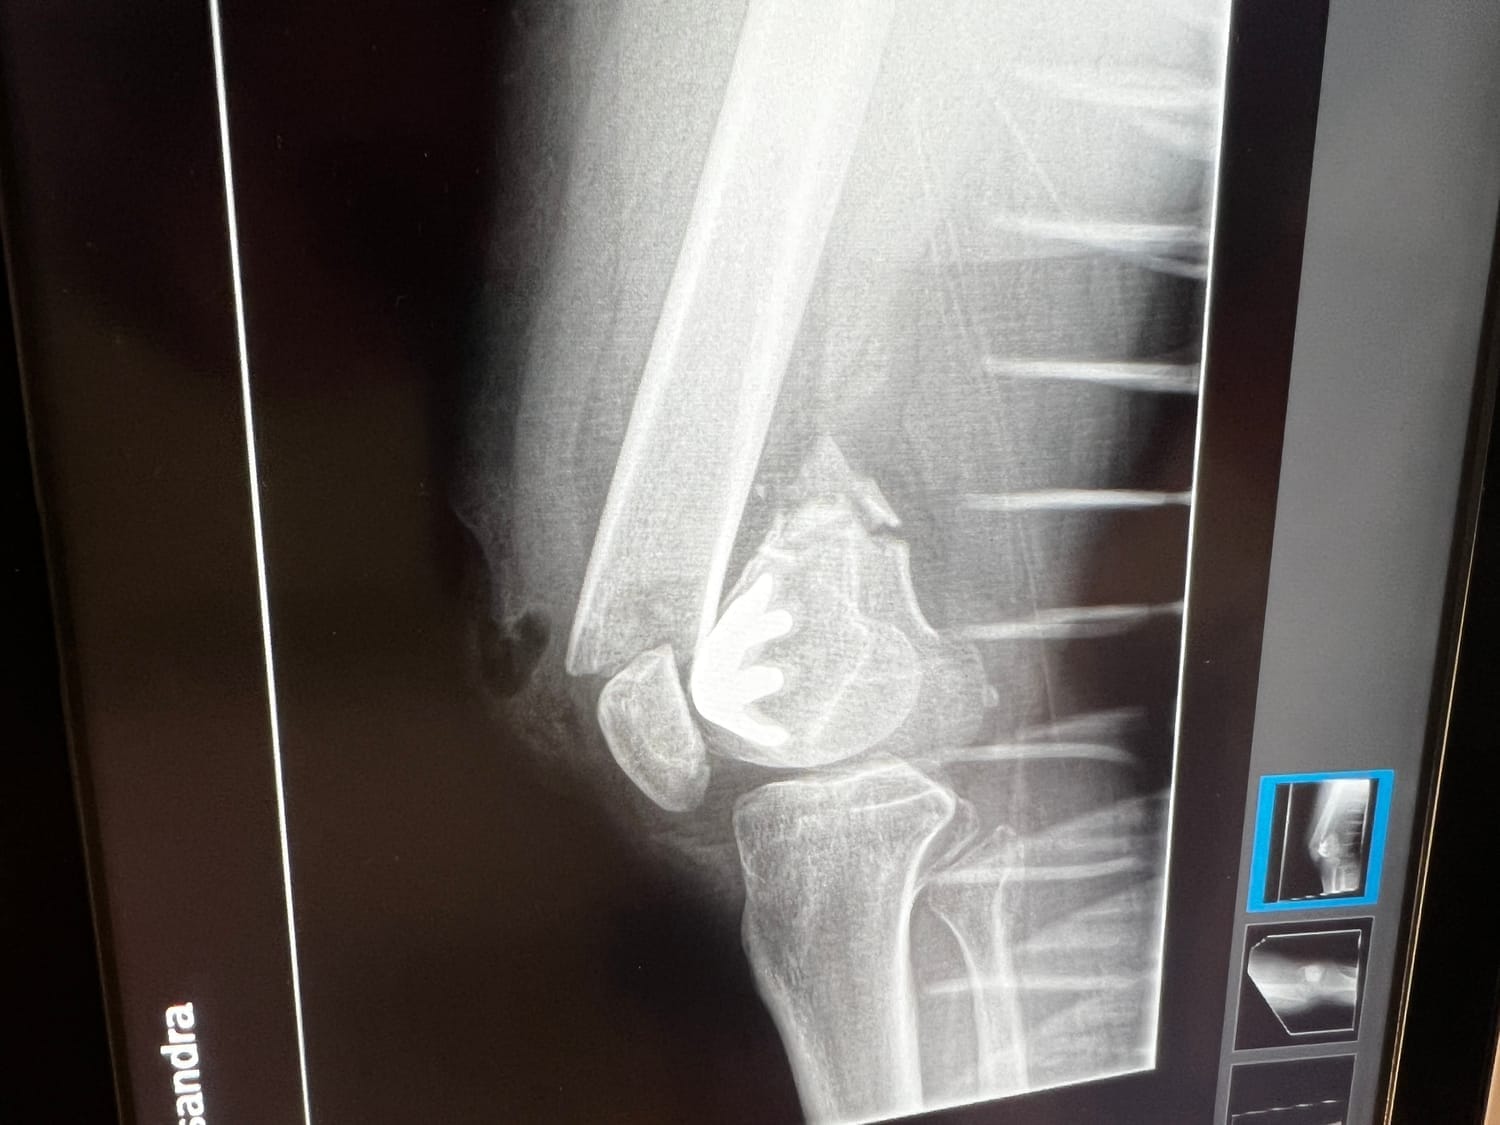

Once at the hospital, the gravity of the situation was revealed; x-rays disclosed the full extent of my injury—a distal femur fracture, and it was an open fracture. This meant that the bone had breached my skin before retracting back inside.

The radiologist informed me that she'd never encountered someone with such a break who hadn’t succumbed to unconsciousness from the searing pain.

For those unfamiliar, an open fracture is particularly perilous due to the high risk of infection.

When a bone breaks through the skin in a non-sterile environment like a farmyard, there is a significant risk of bacteria entering the wound. This can potentially result in severe bone infections that may lead to drastic measures such as amputation or worse outcomes.